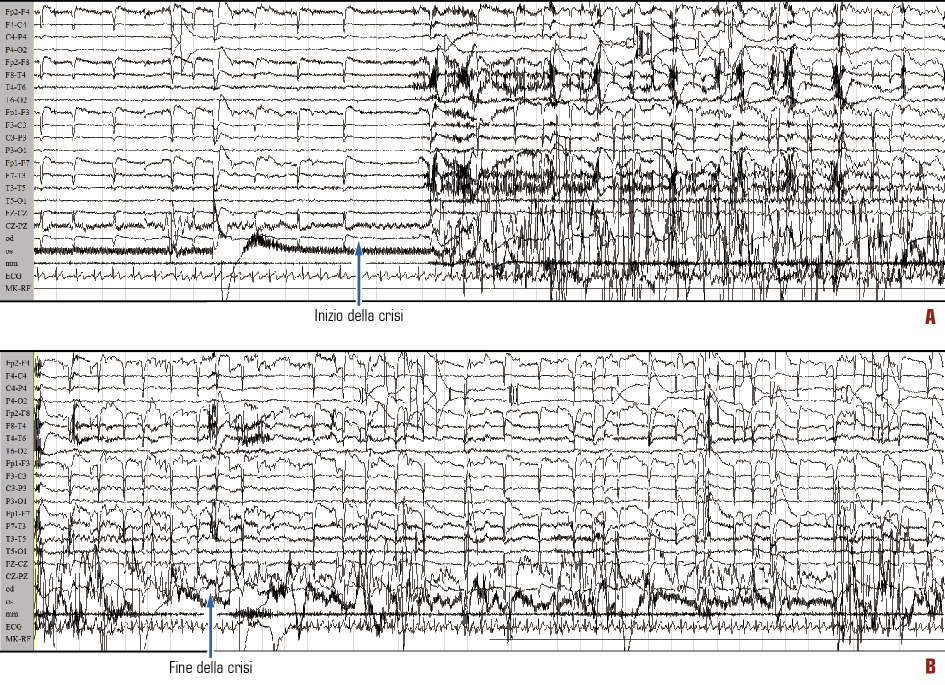

Nel sospetto che si trattasse di crisi epilettiche, la paziente è stata sottoposta ad ulteriori approfondimenti clinico-strumentali con monitoraggio EEG prolungato, EEG dinamico ambulatoriale e RM encefalo con magnete a 1.5 T. Il monitoraggio EEG ha registrato un episodio critico parziale complesso, caratterizzato da perdita del contatto con l’ambiente, pallore, tachicardia, ammiccamenti palpebrali ripetuti, basculamento antero-posteriore del tronco e automatismi semplici di strofinamento delle mani sulle cosce e masticatori, con successivo rapido recupero della coscienza. Nel contesto di artefatti muscolari e da movimento, il tracciato EEG ha mostrato un ritmo beta-alfa-teta reclutante sulle regioni fronto-temporali sinistre, con successiva diffusione rapida a tutto l’emisfero omolaterale e alle regioni anteriori controlaterali (Figura 1).

Figura 1. Monitoraggio EEG: registrazione di una crisi parziale complessa (il tracciato B è la prosecuzione del tracciato A, riportato sotto anziché di seguito per esigenze di spazio). Da notare anche la traccia ECG, che conferma l’incremento della frequenza cardiaca durante e dopo la crisi